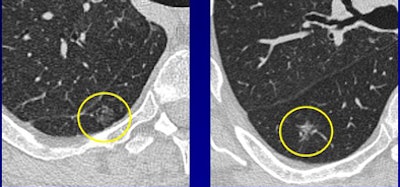

Distinguishing benign from malignant GGOs is a hit-or-miss task for CT, one that could potentially improve if researchers are able to find reliable signs of malignancy or benignity, thereby reducing the need for invasive biopsy.

Overall, the researchers found that patient age, persistence of GGOs over time, irregular shape, the presence of pleural retraction, and other factors generally yielded a higher risk of malignancy. However, some features such as large size, normally suggestive of an elevated malignancy risk, were also associated with benign etiologies, highlighting the need for frequent follow-up.

In another ECR presentation, Dr. Chang Min Park from Seoul National University Hospital in South Korea discussed a study to compare clinical and thin-section CT findings of malignancy and benignity in GGOs.

The study was limited to pure nodular ground-glass opacities (pnGGOs) that did not resolve during a six-month follow-up.

"PnGGOs have been reported to consist of 5.5% to 12% of all CT-detected pulmonary nodules, but pnGGOs are a kind of nonspecific CT finding," Park said. When pnGGOs persist, they have a suggestion of malignancy, but even most of these are benign.

Studies have shown pnGGO malignancy rates of 18% to as high as 48%, but biopsy is often necessary to find the malignant lesions. What's needed is an "accurate estimation between malignant and benign pnGGOs in order to reduce the number of unnecessary surgeries," Park said. "However, most studies had small populations, and do not provide practical differentiation points" between benign and malignant lesions.

Patients with malignancy were significantly older than those with benign lesions (57.83 ± 8.57 years versus 52.19 ± 10.71 years, p = 0.005). Unlike the Ferretti study, but in line with most previous research, the size of malignant lesions was larger than that of benign lesions (10.37 ± 5.74 mm versus 7.93 ± 5.01 mm, p = 0.026). Lesion size 8 mm or larger was determined to be the optimal threshold for differentiating malignancy and benignity with balanced sensitivity and specificity.

In addition, malignant lesions were more likely to show pleural retraction, bubble lucency, or air bronchogram (p = 0.035). Significant associations between malignancy and patient age (odds ratio, 1.061), lesion size 8 mm or larger (odds ratio, 2.784), and the presence of pleural retraction, bubble lucency, or air bronchogram (odds ratio, 4.414) were found. With these characteristics, the differentiating performance of multiple logistic regression models was relatively good (area under the curve [AUC] = 0.762).

"There was a significant difference between patients with malignant pnGGO and those with benign pnGGO in terms of patient age," Park said. Other significant differences between malignant and benign pnGGOs were seen in lesion size and the presence of pleural retraction. "Size larger than 8 mm was an independent estimator of malignant and benign pnGGOs," he said.